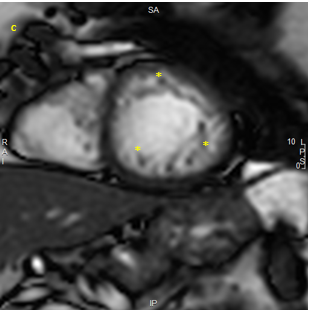

At the same time a new MRI of the heart showed remission of dilated myocardiopathy, EF 57% and unchanged trabeculation in the apical part of the left ventricle (Figures 1&2). NT Pro BNP 463 pg/ml (normal values less than 450).

Figure 1 MRI apical short axis image at end-diastole 2023 showing trabeculations (asterisk) and decreased systolic function.

Figure 2 MRI apical short axis image at end-diastole 2024 showing the unchanged trabeculation (asterisk) and improvement of systolic function.